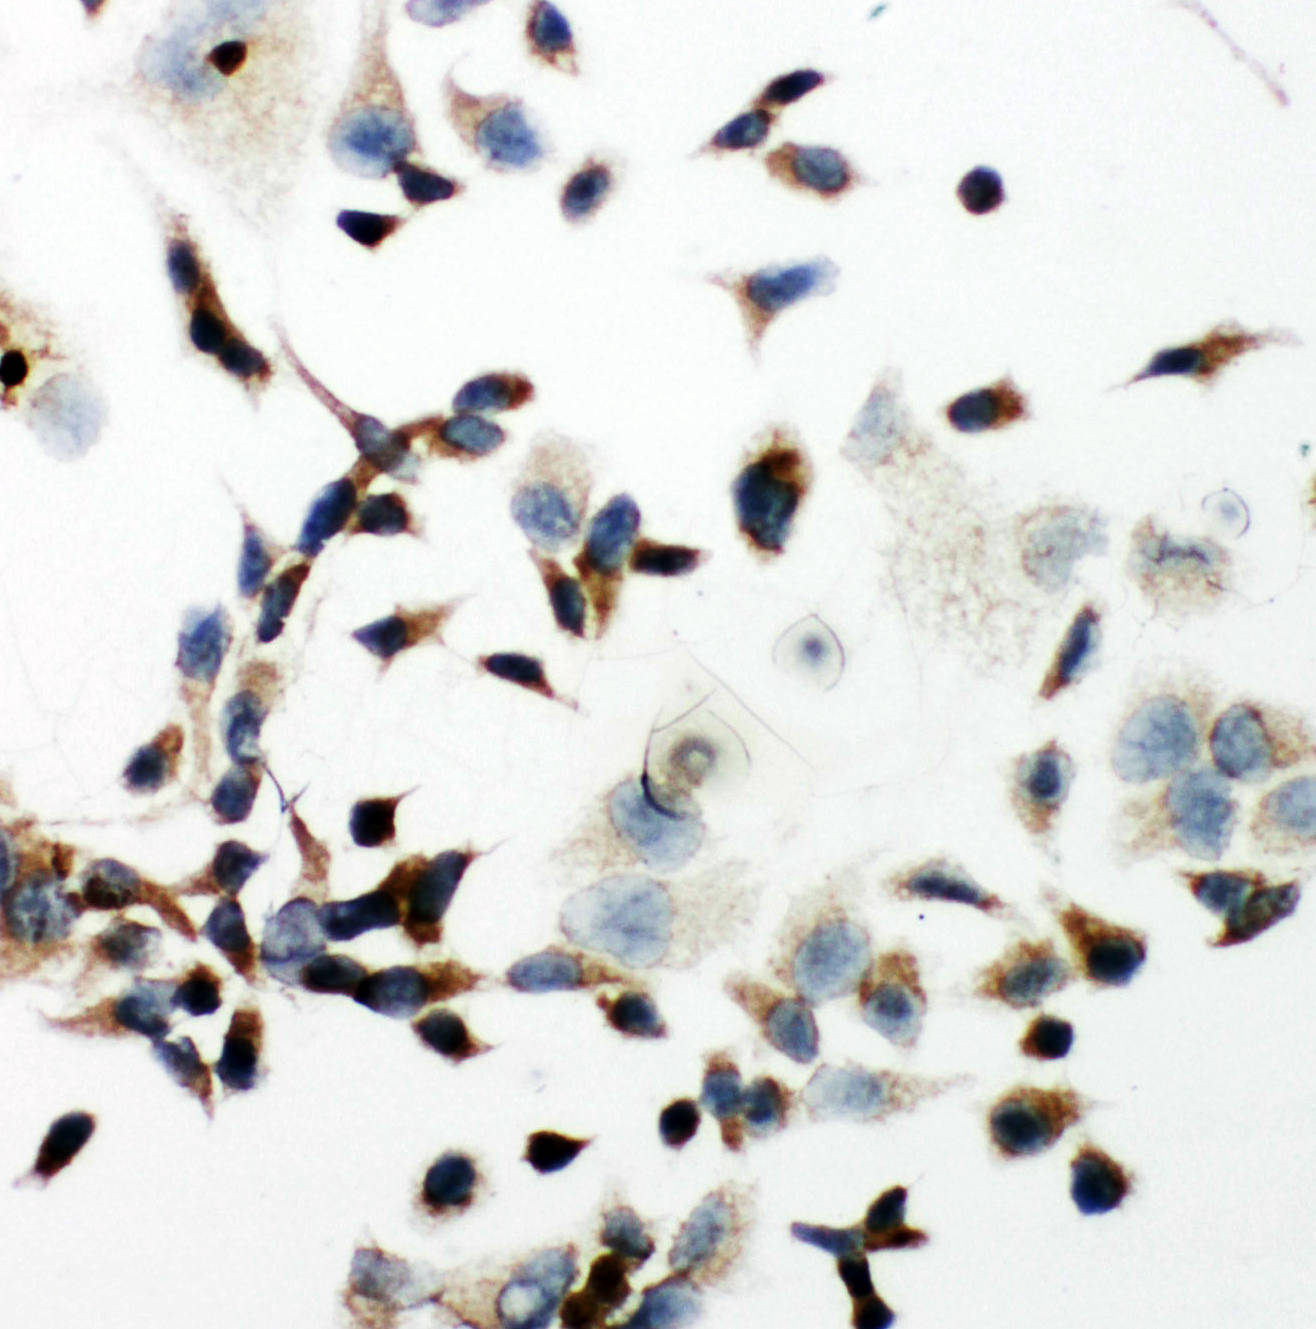

ICC analysis of VEGFR2/KDR using anti- VEGFR2/KDR antibody (BA0472).

VEGFR2/KDR was detected in an immunocytochemical section of Hela cells. The section was incubated with rabbit anti-VEGFR2/KDR Antibody (BA0472) at a dilution of 1:100. Biotinylated goat anti-rabbit IgG was used as secondary antibody. The section was developed using Strepavidin-Biotin-Complex (SABC)(Catalog # SA1022) with DAB (Catalog # AR1027) as the chromogen.